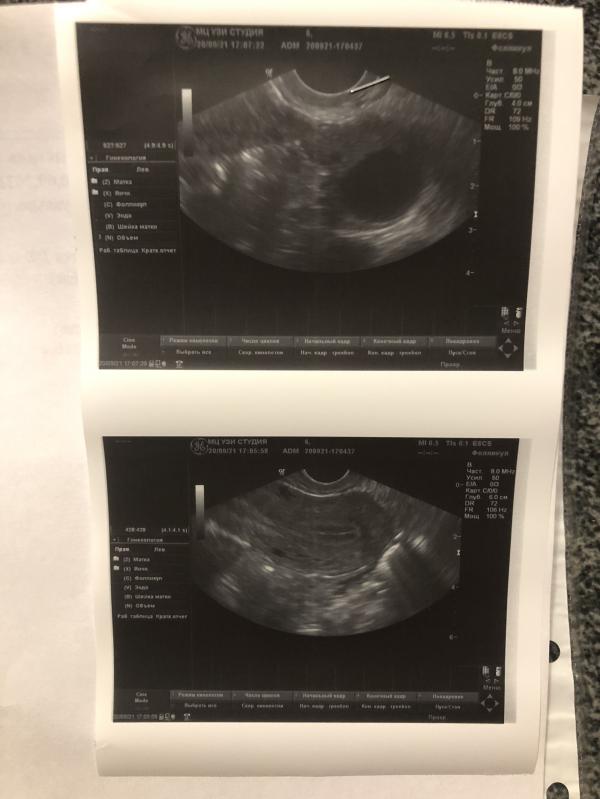

post image 1

post image 2

В этом цикле решила сделать фоликуллометрию)

Врач сказала, что эндометрий красивый )

Фолликул в течении 1-3 дней должен лопнуть.